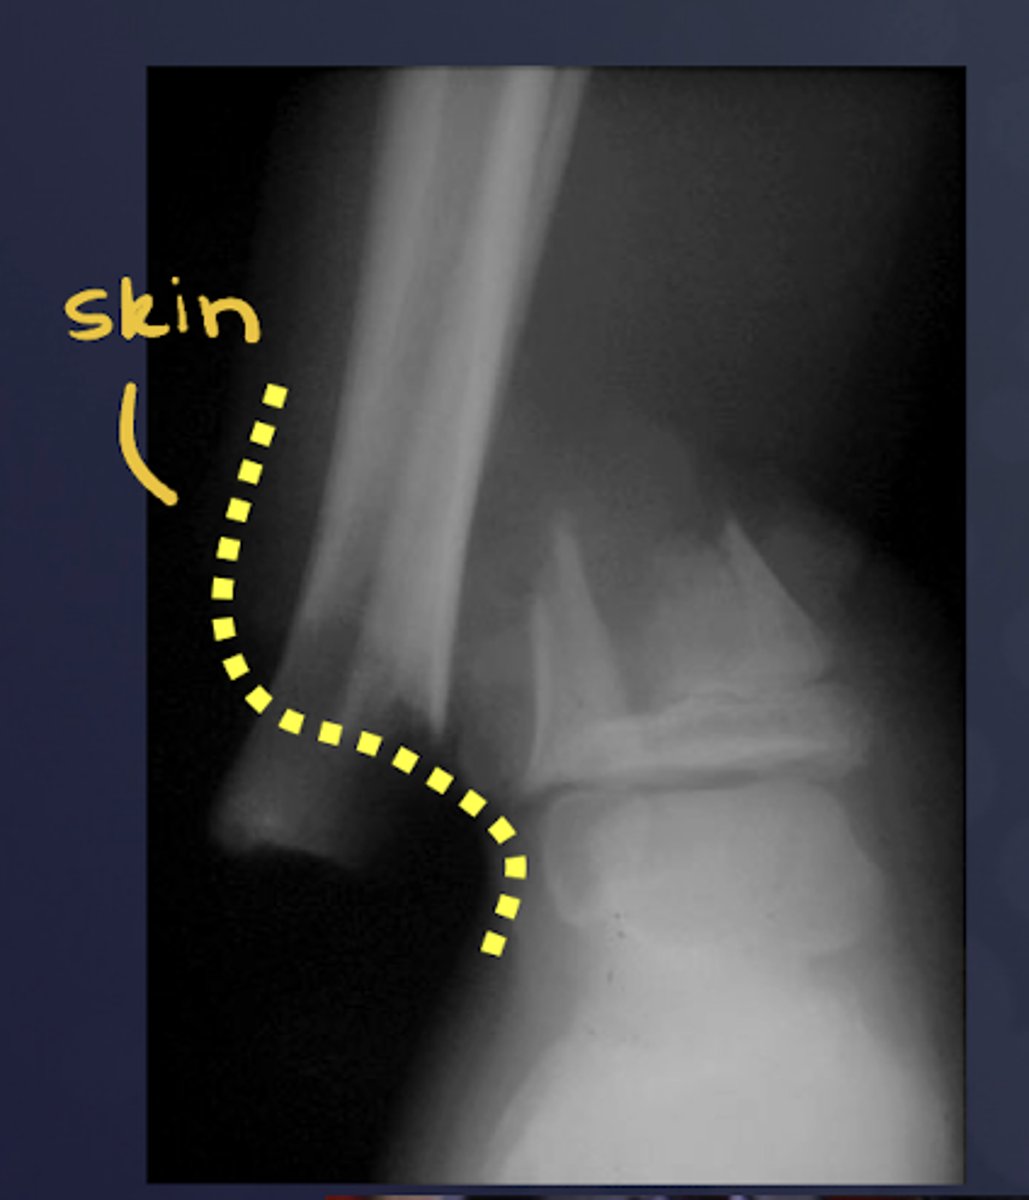

What is the extent of fracture?

Open vs. closed